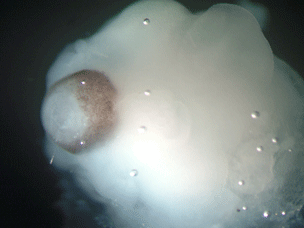

Now, however, a team of researchers at the Austrian Academy of Sciences Molecular Biotechnology Center have successfully grown miniature human brains in the laboratory.

The method, published in the journal Nature this week, reproduces the earliest developmental stages of the human brain. Human stem cells were induced to form embryonic "Neural Tubes" or neuroectoderm -- the beginning developmental stage of the human nervous system. These were then "placed in tiny droplets of gel to give a scaffold for the tissue to grow" and cultured in a nutrient and oxygen filled "bioreactor." The neural tubes continued to develop, differentiating into several of the separate specialized regions of the brain: the cerebral cortex, the retina, and,in one case, a developing hippocampus.

The tissues grew to their maximum size (4 mm) in two months and survived in the laboratory for about a year. They didn't develop any further as there was no blood supply, but the scientists think they paralleled closely the development of a 9-week-old human fetus. The research team names these structures "Cerebral Organoids," as they are incomplete, in no way fully developed brains and incapable of consciousness. As the neural tissues aren't allowed to forn a fully functioning brain, the researchers don't feel that there are ethical issues with this research. They are, however, opposed to allowing the "cerebral organoids" to develop any further.